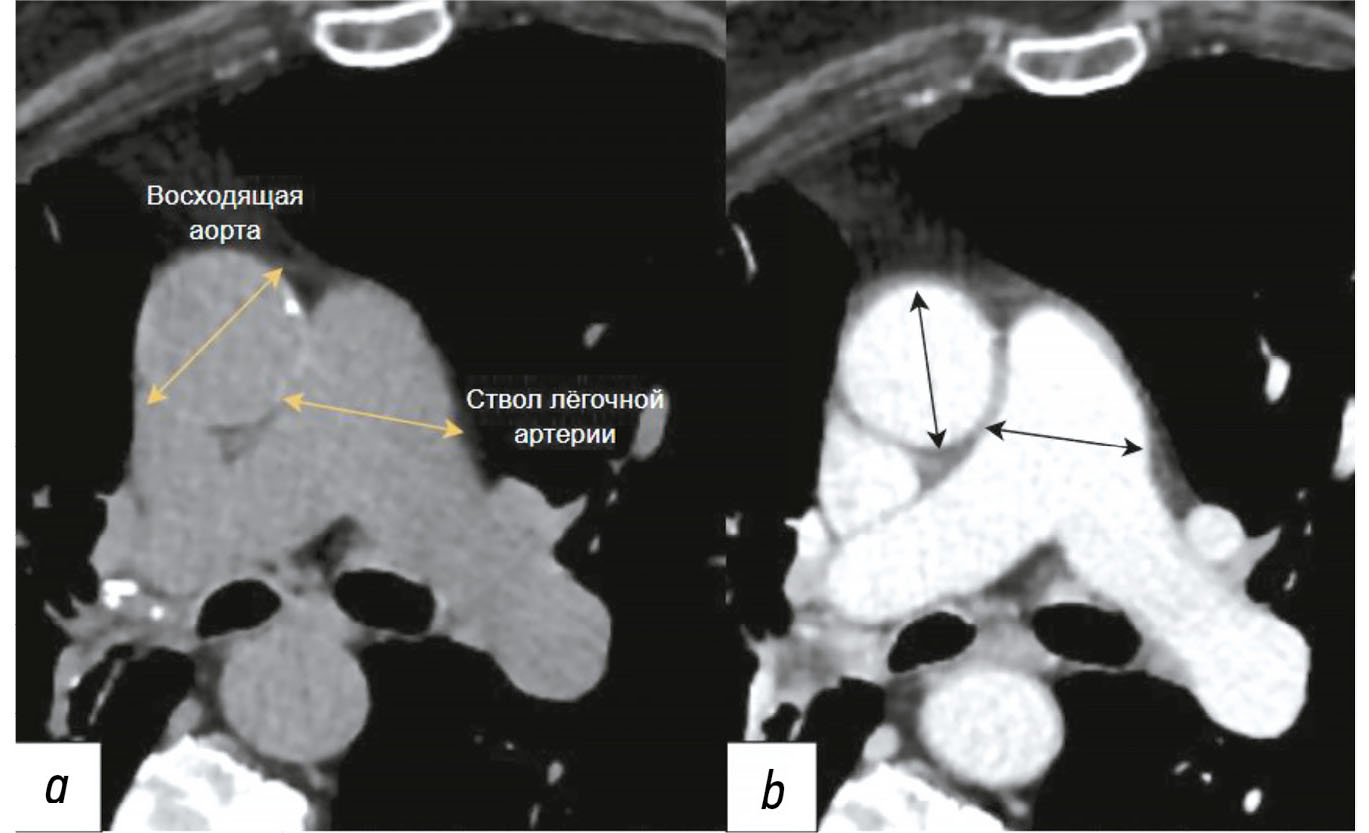

Diagnosis of thoracic aortic aneurysms and pathological pulmonary trunk dilation using chest computed tomography and artificial intelligence: modern approaches and prospects (a review)

Abstract

Early diagnosis of thoracic aortic aneurysms and pathological pulmonary trunk dilation is crucial to prevent severe complications, including vascular wall rupture and acute right ventricular failure, and reduce cardiovascular mortality. This review examines contemporary imaging approaches for these conditions, focusing on computed tomography as the gold standard modality. Emphasis was placed on the implementation of artificial intelligence technologies, which enable automatic segmentation of vascular structures, measurement of their diameter, and opportunistic screening, allowing early detection of asymptomatic conditions without additional diagnostic procedures, thereby reducing radiologist workload and improving medical care quality. The study comprehensively analyzed the Moscow Experiment, wherein the application of artificial intelligence in medical image analysis showed high sensitivity, reproducibility, and reduced reporting time. Despite these significant advantages, the need for expert supervision of artificial intelligence-generated results to ensure diagnostic accuracy and reliability is emphasized. Moreover, the review highlights the importance of adapting algorithms to different scanning protocols and population-specific features. Additionally, the importance of interdisciplinary collaboration among cardiologists, radiologists, data scientists, and software developers for the effective integration into routine clinical practice is pointed out. Therefore, the review outlines the potential of artificial intelligence technologies to enhance diagnostic quality and underscores the need for further clinical research and standardization of methods for successful integration into daily practice.

286-301